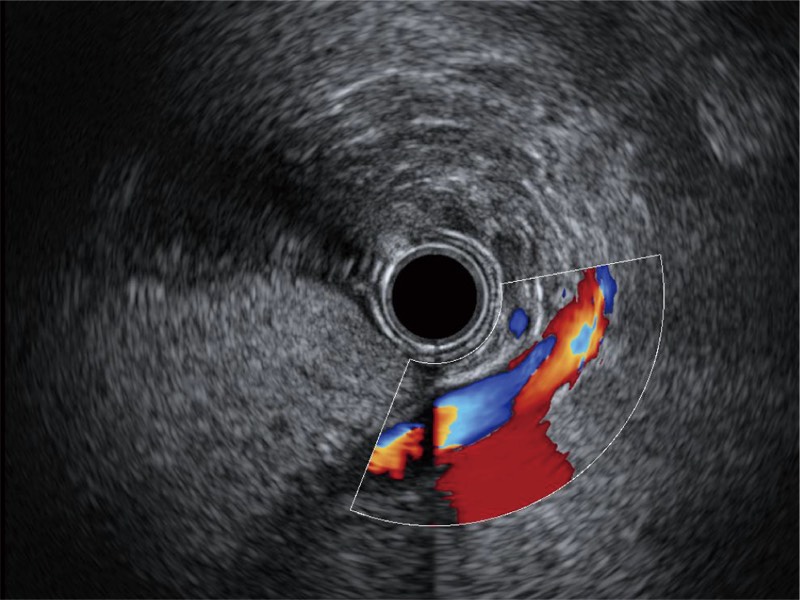

肝左叶和肝静脉的横截面